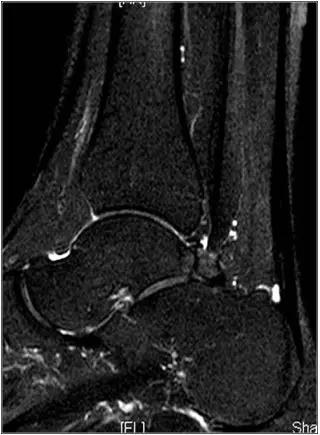

男,11岁,自述后踝下方疼痛,活动时为甚,并有一突起。

- MRI 检查示距后三角骨及周围软组织有水肿信号,距后三角骨和距骨之间正常的低信号纤维连接中断,出现液性信号。

3、MR表现:

- 三角籽骨或距骨后三角结构模糊和变形,T1WI信号降低, T2WI信号升高,

- 周围脂肪水肿,

- 踇趾长屈肌腱信号升高,见鞘膜积液,

- 胫骨后下跟骨上缘骨结构形态变化和信号异常,

- 三角籽骨和距骨退行性囊变。

三角籽骨综合征并跟腱滑囊积液